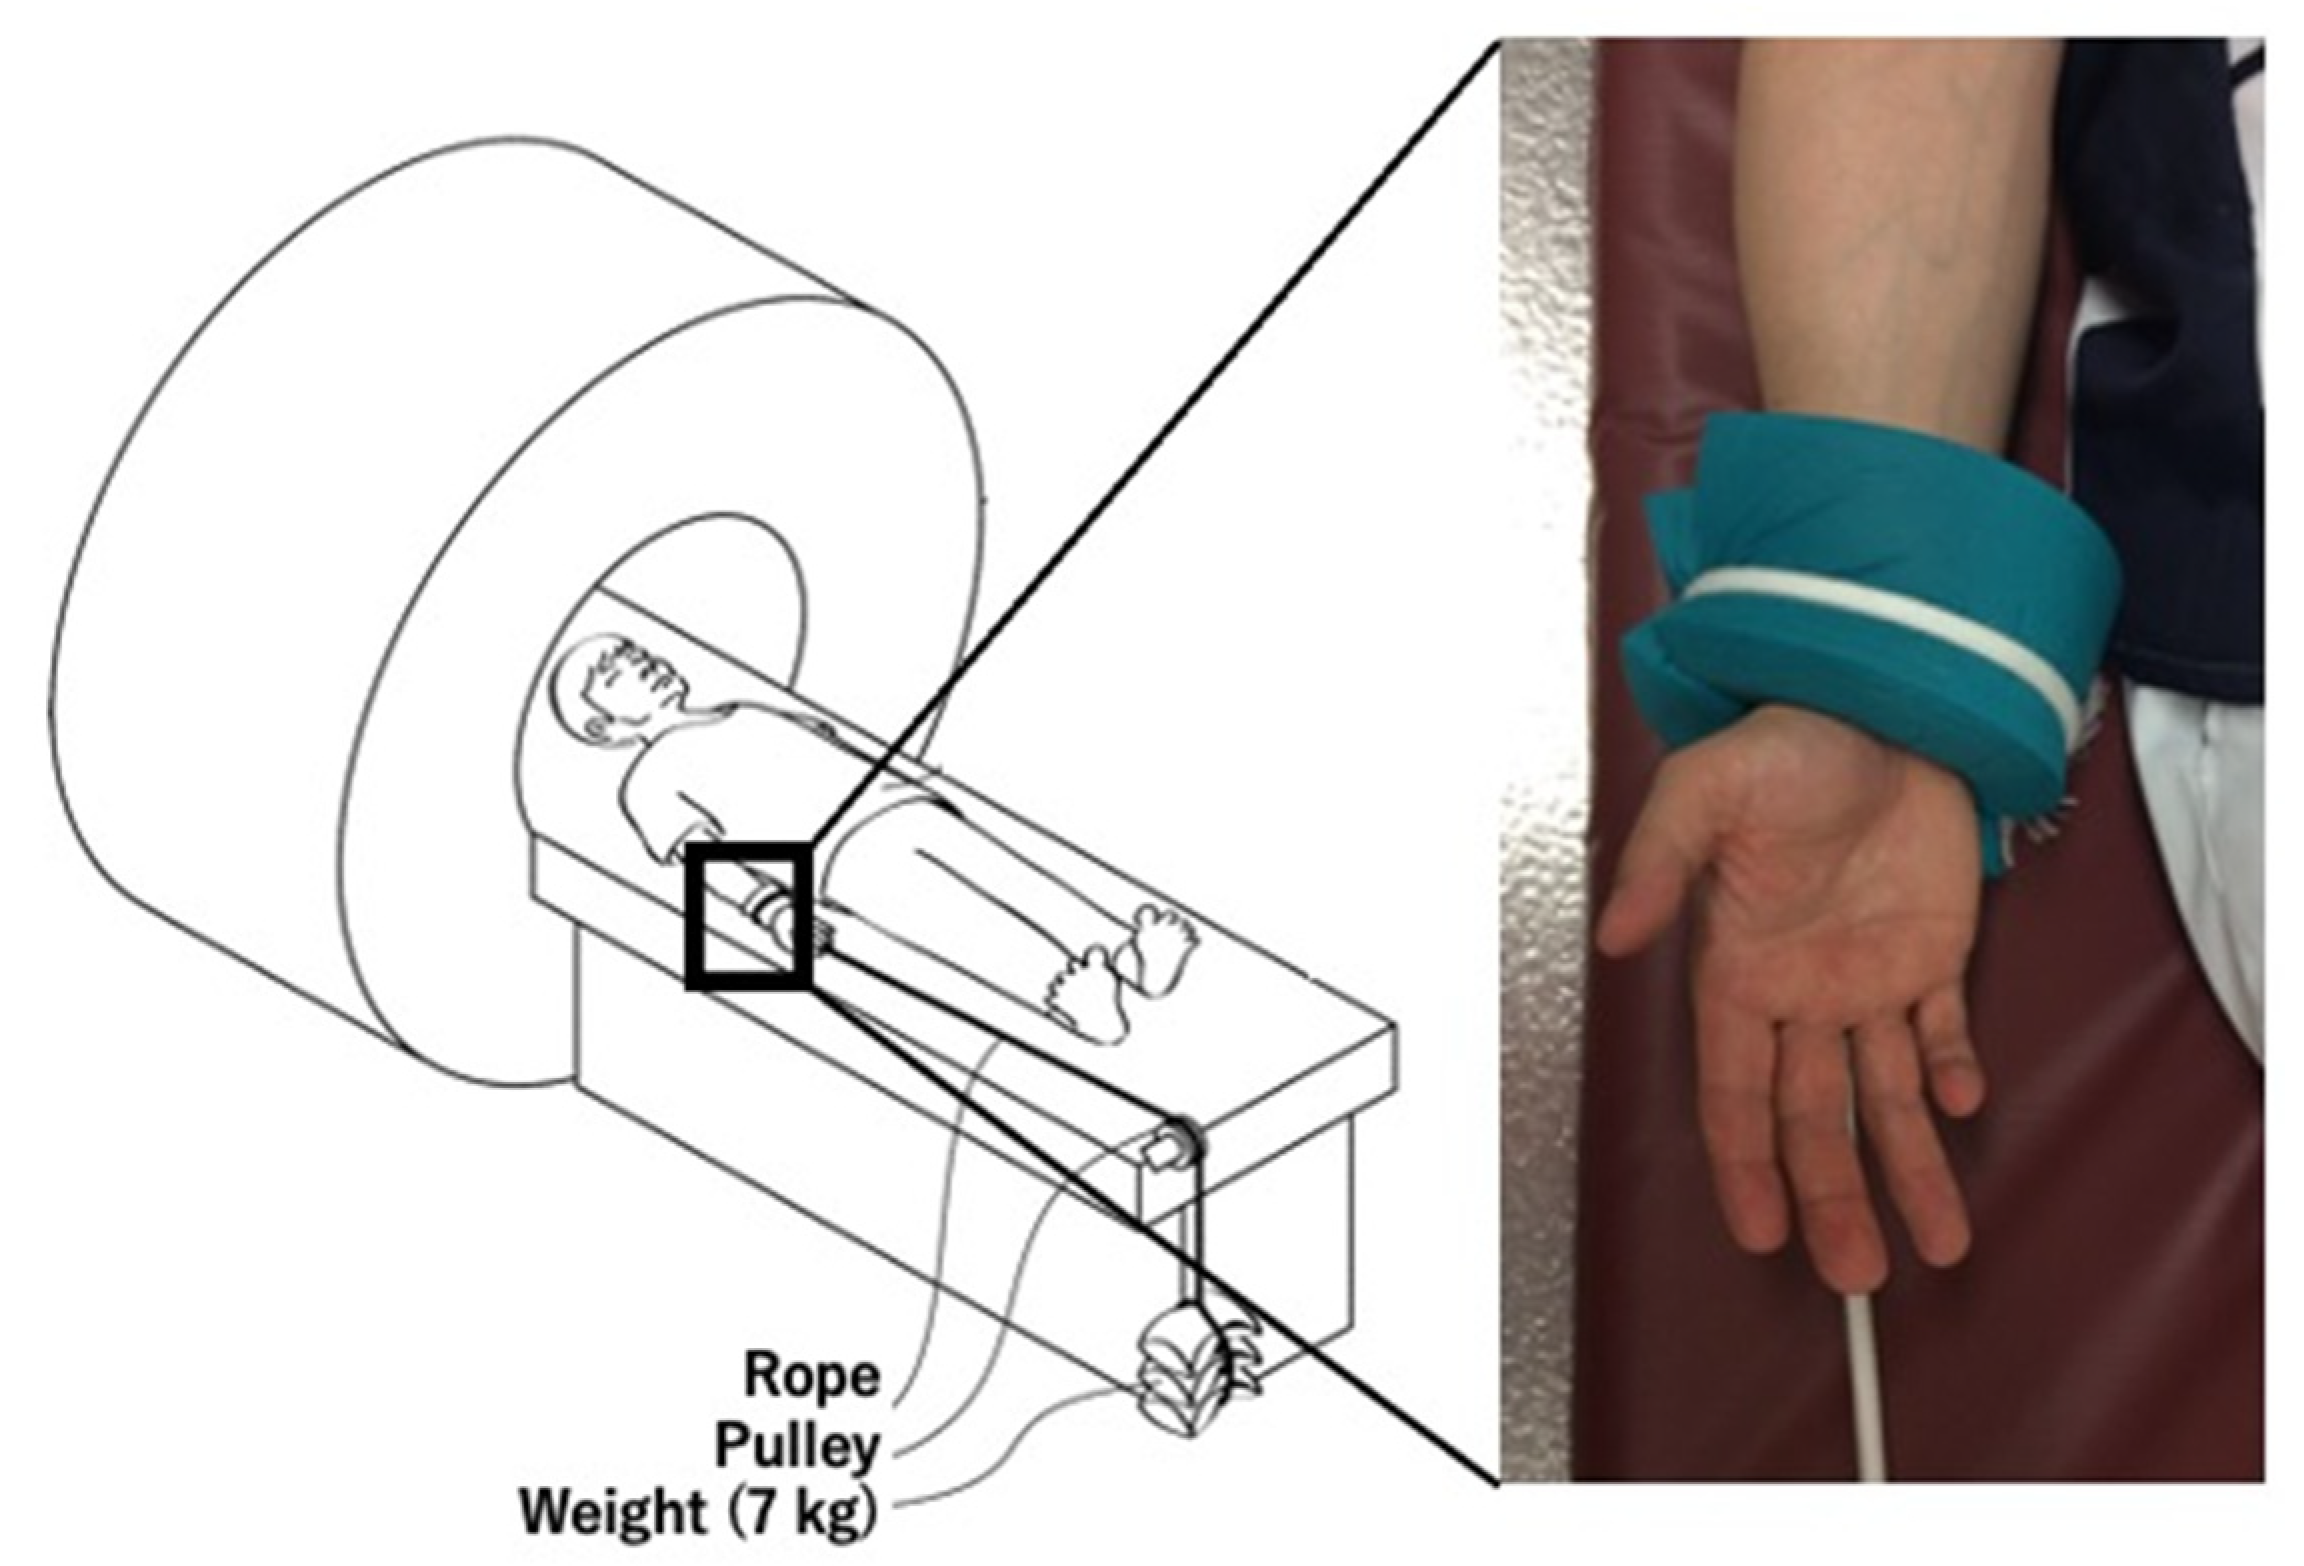

2.2. Obtaining the MR and CT Images

- Kohyama, S.; Tanaka, T.; Shimasaki, K.; Kobayashi, S.; Ikumi, A.; Yanai, T.; Ochiai, N. Effect of elbow MRI with axial traction on articular cartilage visibility-a feasibility study. Skelet. Radiol. 2020, 49, 1555–1566. [Google Scholar] [CrossRef]

- Lee, R.K.; Griffith, J.F.; Yuen, B.T.; Ng, A.W.; Yeung, D.K. Elbow MR arthrography with traction. Br. J. Radiol. 2016, 89, 20160378. [Google Scholar] [CrossRef] [Green Version]